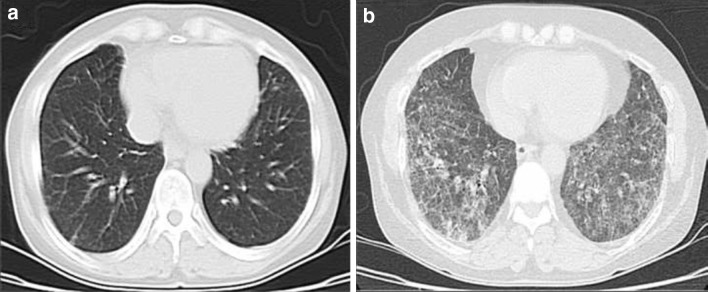

Fig. 1.

a Baseline thorax computed tomography image before the cyclophosphamide treatment. b Reticular interstitial infiltration with honey-comb appearance after the treatment

A 52-year-old woman was admitted to our hospital with persistent fatigue and pretibial edema. Serum creatinine was 2.7 mg/dL, and urine analysis revealed hematuria and pyuria. Proteinuria was 3 g/day. Tests for anti-neutrophil cytoplasmic antibody (ANCA) and anti-glomerular basement membrane antibody were negative. Based on renal biopsy, ANCA-negative pauci-immune crescentic glomerulonephritis was diagnosed. No abnormal findings were apparent on the baseline thorax computed tomography (CT) image (Fig. 1a). The patient was started on a pulse methylprednisolone regimen (1 g/day for 3 days) followed by 750 mg cyclophosphamide (CPA) per month. Following the pulse treatments, 1 mg/kg prednisolone was continued for an additional month, with tapering of the steriod dose by 4 mg/week. The maintenance dose of methyprednisolone was 4 mg/day. After the third dose of CPA, patient complained of exertional dyspnea and cough. The serum creatinine level and urinalysis results were normal. However, a second thorax CT showed the presence of a reticular interstitial infiltration with a honey-comb appearance (Fig. 1b). As the concomitant use of certain drugs is able to induce interstitial lung disease, we investigated this possibility but found no suspicious drug history. Infectious etiologies as possible causes of the clinical picture were also considered and subsequently excluded. The diagnosis of CPA-induced early-onset interstitial lung disease was established on clinical and radiological grounds. The CPA was withdrawn from the therapeutic regimen, and treatment with 1 mg/kg prednisolone was started. At follow-up, the dyspnea and cough had disappeared. Baseline and follow-up serum C-reactive protein levels after the treatment were 11.2 and 1.1 mg/dL, respectively.